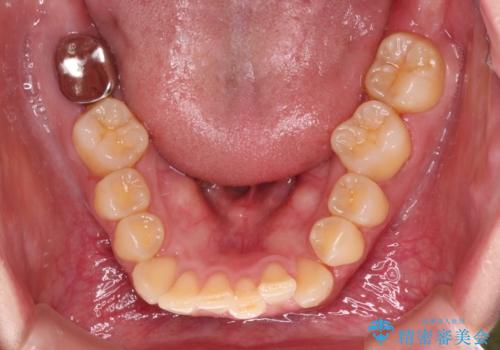

インビザライン単体で対応ることも検討できますが、達成する可能性が低いため、カリエールディスタライザーという補助装置を併用して、より確実性を上げることとしました。

奥歯の咬み合わせと深い咬み合わせを改善した後、インビザラインで歯列を整えることとしました。